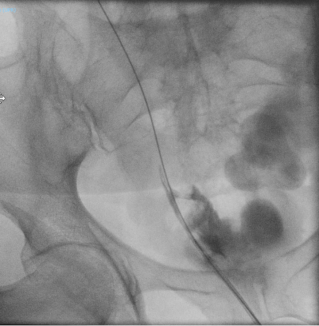

A 57-years-old female was referred to general surgeons for port implantation before starting chemotherapy. Catheter insertion was planned on the right cephalic vein, but its progression proved impossible during the procedure. A right subclavian vein puncture was subsequently performed, allowing the guidewire to cross the right brachiocephalic vein and descend to left side of the heart. While suspecting incorrect placement, the right internal jugular vein was punctured under ultrasound control, yet the guidewire advanced laterally toward the left heart. Upon vascular consultation, images review of previously conducted scan revealed a patent PLSVC, which transversed posteriorly to the left atrium and drained into the right atrium through the coronary sinus. The right SVC was absent, replaced by a left brachiocephalic vein bridge that drained into the PLSVC (Figure 1). The catheter was placed into the PLSVC and the procedure completed (Figure 2). The patient developed a pneumothorax due to subclavian puncture, which was effectively managed by drainage placement, leading to an uneventful recovery.